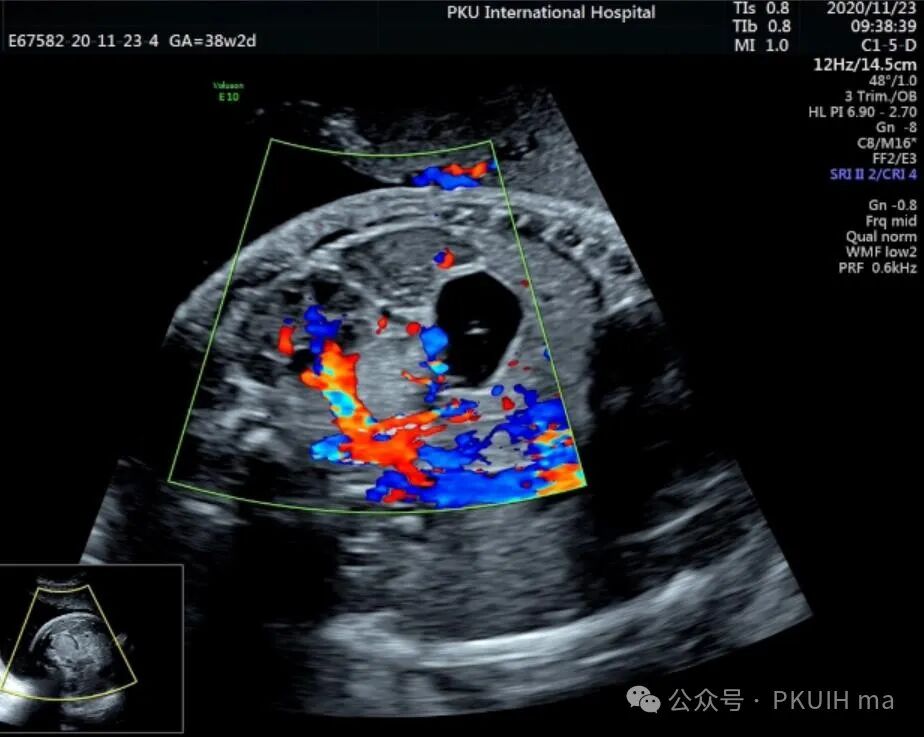

神经母细胞瘤是儿童时期最常见的肿瘤之一,其发病率为1/10,000 -30,000儿童。神经母细胞瘤可在妊娠晚期被诊断出来。产前诊断的肿瘤往往较小,90%涉及肾上腺。囊性和实性区域是典型的,可伴有出血和坏死。囊性病变预后较好。神经母细胞瘤可有微钙化,伴有声影、完整包膜和造成肾脏下移。这些肿瘤可能出现在颈部、胸部或腹部椎旁交感神经节的其他部位。引起气道压迫的宫内病变已有报道。肾上腺肿块伴肝肿大提示神经母细胞瘤的诊断。

上图是一例在孕晚期发现的肾上腺占位,生后病理证实为神经母细胞瘤的患儿,生后及时做了治疗预后非常好,目前宝宝各项指标都很好。

这几年我们在孕晚期发现有3例神经母细胞瘤胎儿,预后都很好。在孕晚期超声中建议常规扫查下胎儿双肾区